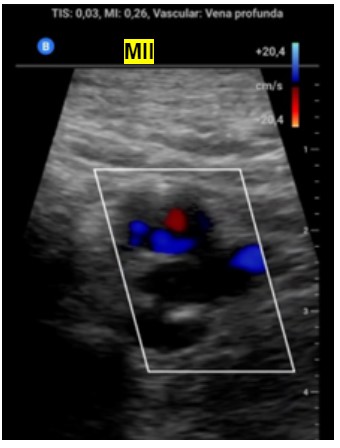

Ante la sospecha de Trombosis venosa profunda realizamos ecografía de compresión venosa de miembros inferiores detectando la falta de colapsabilidad de la femoral común y femoral superficial del miembro inferior derecho, cosa que no pasaba en el izquierdo.